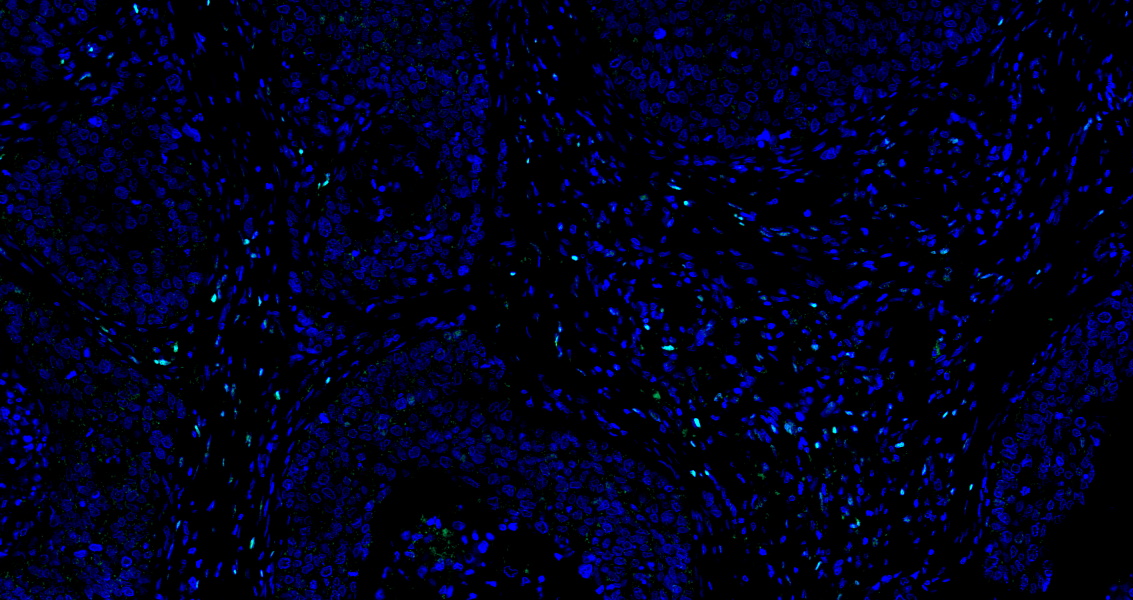

• Tyramide signaling amplification based immunofluorescence was performed on paraffin-embedded human Esophageal Carcinoma tissue using FOXP3 antibody. Antigen retrieval was performed in EDTA buffer pH 9.0 (95 °C, 20 min) followed by cooling to RT. Then incubated with primary antibody (HY-P80965, 1:100 dilution) at room temperature for 60 minutes and HRP conjugated secondary antibody for 10 minutes. Fluorescence was then developed with TSA520. The tissues were counterstained with DAPI and mounted with Anti-fade mounting medium.